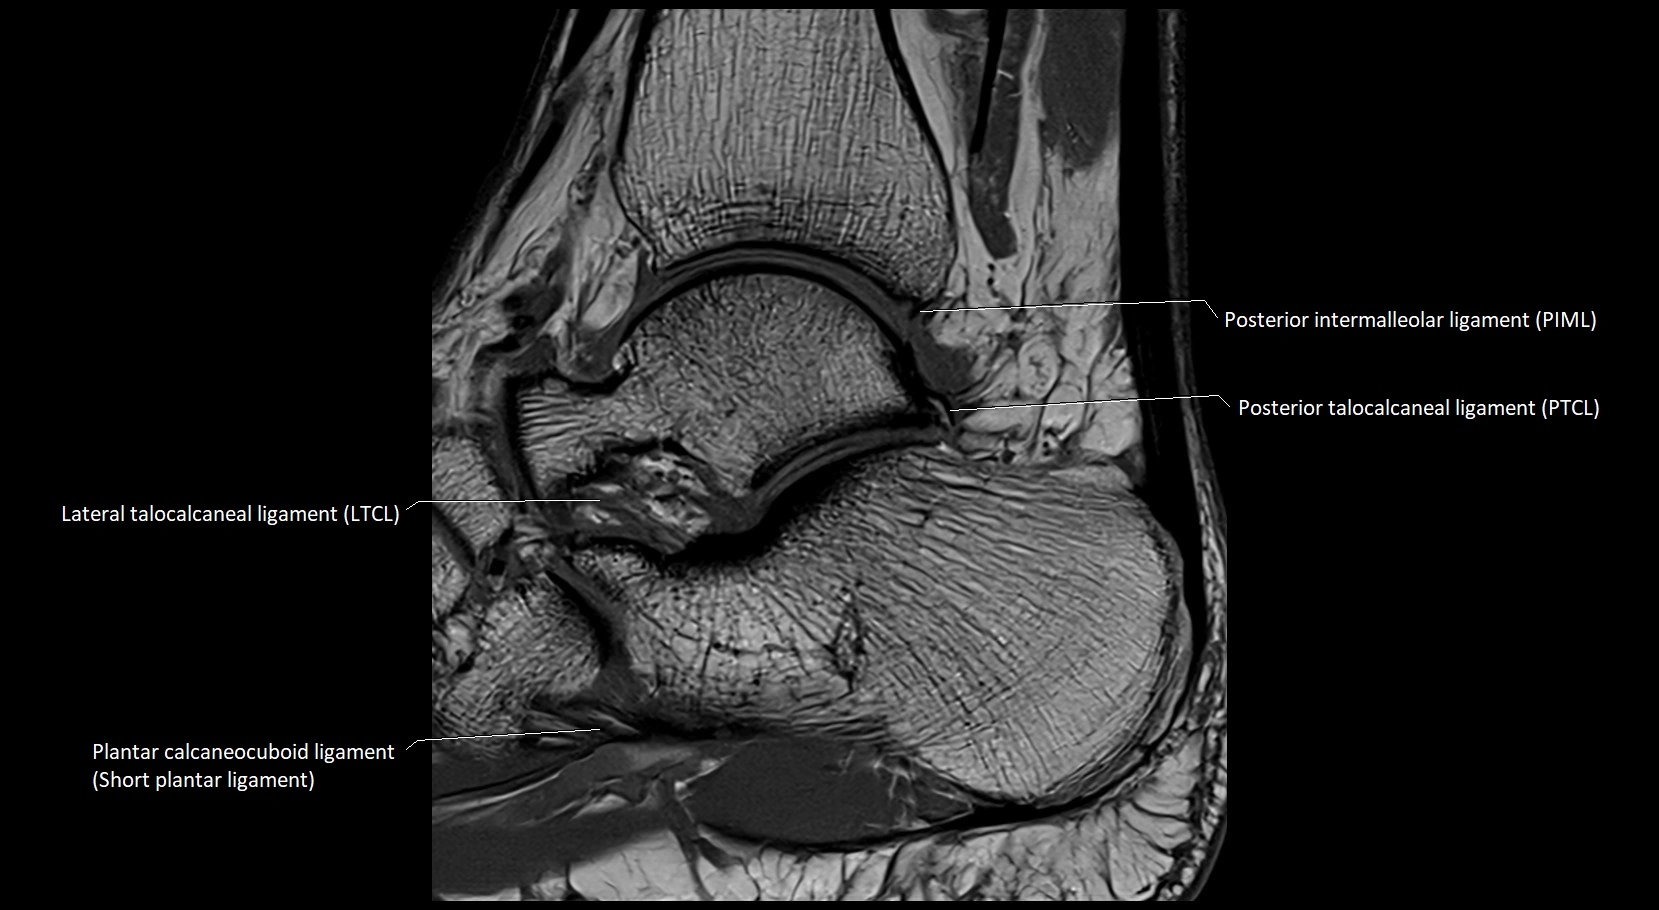

MRI image

image